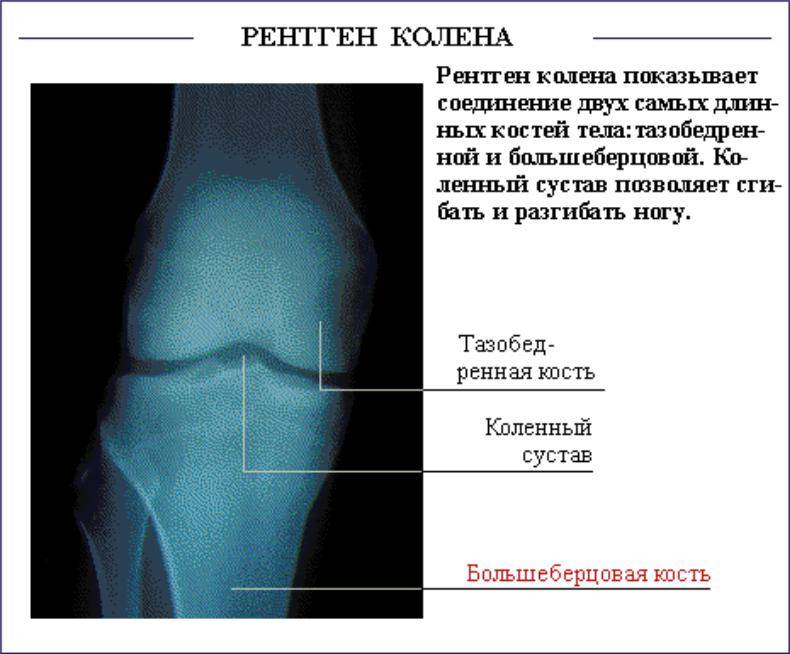

Рентгенограммы здорового коленного сустава: полезные советы и фотографии

На этой странице вы найдете подборку фотографий рентгенограмм здорового коленного сустава, а также полезные советы, которые помогут вам лучше понять, как выглядит нормальное состояние этого важного сустава.

Нормальная рентген-анатомия коленного сустава